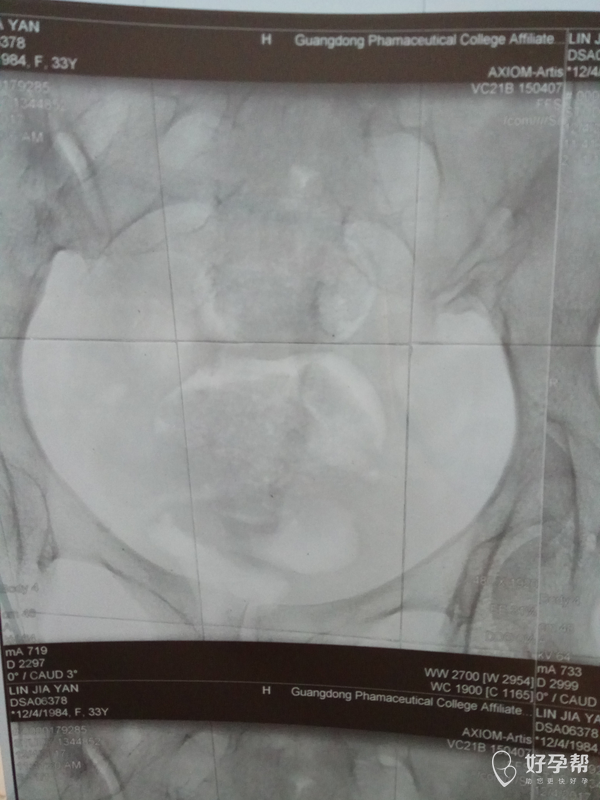

医生帮我看看造影照片,

这是碘油造影吧,双侧输卵管都是通畅的,建议积极试孕,祝好孕